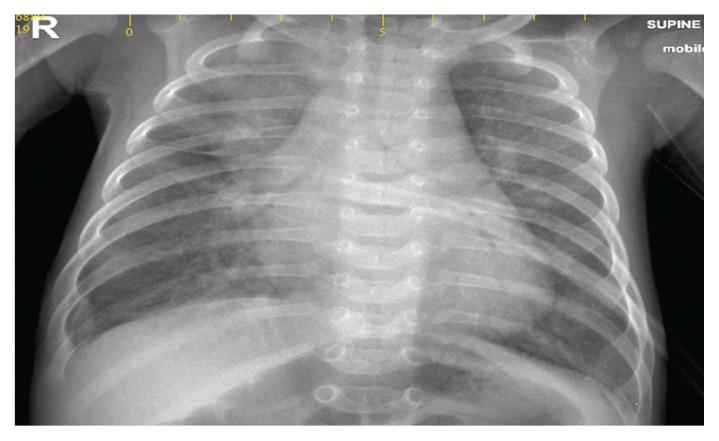

Cor triatriatum sinistrum (CTS) is a rare congenital cardiac anomaly characterised by an abnormal septum within the left atrium impairing blood flow to the left ventricle. We report the case of a two-month-old male infant who presented with symptoms of heart failure since the age of two weeks. He was admitted to a local hospital and was managed with antibiotics because of the impression of pneumonia. Due to persistent unresolved tachypnoea and tachycardia, he was referred to Sultan Qaboos University Hospital, Muscat, Oman, in 2019 for cardiac evaluation which confirmed a diagnosis of isolated CTS with severe stenosis and pulmonary hypertension. He underwent an urgent surgical excision of the membrane with uneventful recovery.

先天性左房三房心(CTS)是一种罕见的先天性心脏畸形,其特征为左心房内异常隔膜,导致血液流向左心室受阻。我们报告了一例两个月大的男性婴儿,他自两周大以来就出现心力衰竭的症状。他被收治到当地医院,由于疑似肺炎,给予了抗生素治疗。由于持续存在的呼吸急促和心动过速未得到解决,他于 2019 年被转诊到阿曼马斯喀特的苏丹卡布斯大学医院进行心脏评估,确诊为孤立性 CTS 合并严重狭窄和肺动脉高压。他接受了紧急手术切除隔膜,术后恢复顺利。